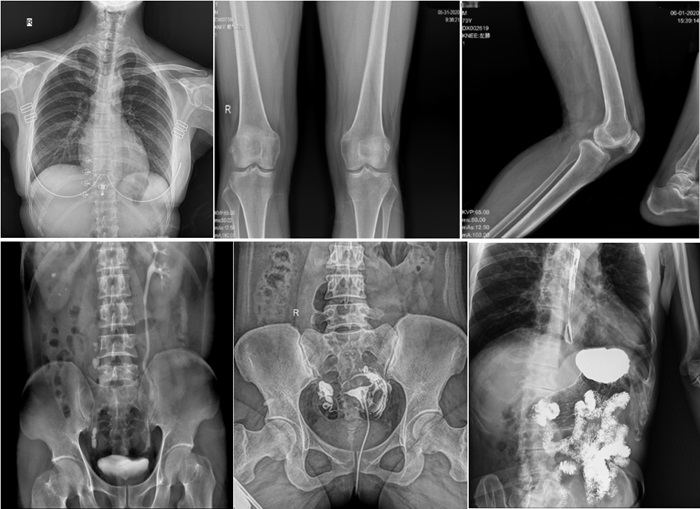

普利德動態(tài)平板DRF作為普放領(lǐng)域最新技術(shù)的代表,融合了攝影、透視和造影等多功能于一體,并能在可視化條件下進(jìn)行高清點片,有效減少了傳統(tǒng)靜態(tài)DR盲拍造成漏診和誤診的風(fēng)險。其17×17英寸大幅面成像,能夠通過一次曝光實現(xiàn)胸部、腹部全覆蓋。設(shè)備支持最高30幀/秒的采集幀率,確保了動態(tài)影像的流暢性,便于醫(yī)生觀察細(xì)微病變,提升診斷精準(zhǔn)性。

在實際應(yīng)用中,普利德動態(tài)平板DRF展現(xiàn)出了多種優(yōu)勢。例如,在胸部影像檢查中,它清晰顯示肺部紋理和結(jié)節(jié),為肺癌早期篩查提供有力支持;在骨科領(lǐng)域,可用于骨折的診斷和復(fù)位效果評估,幫助醫(yī)生制定更精準(zhǔn)的治療方案;在消化系統(tǒng)檢查中,能有效發(fā)現(xiàn)胃腸道疾病的異常。